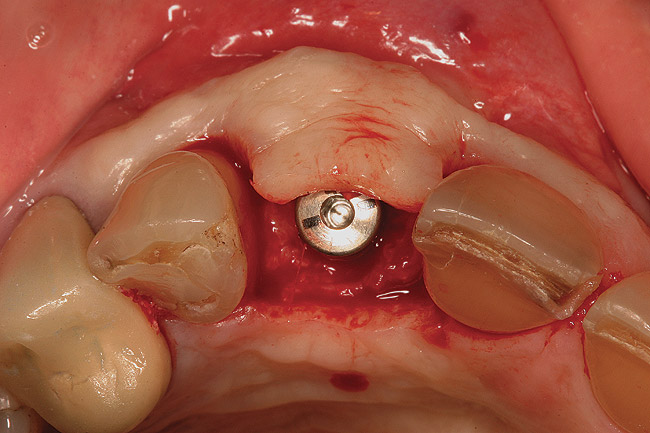

Figure 2  (Case 1) Condition of implant at surgical exposure.

Figure 2